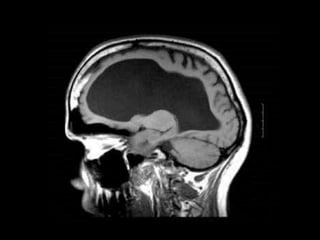

It is a defective condition characterized by the

accumulation of fluid within the ventricles or between

the membranes of the brain.

Brain damage follows from the pressure build-up

from the fluid that cannot escape, resulting in the

death of the child.